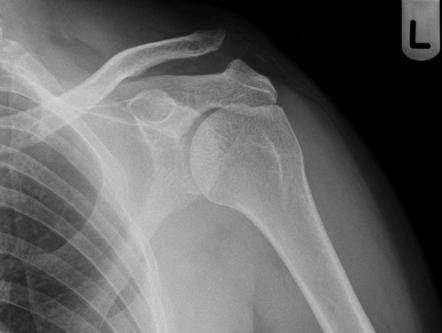

- Nhìn thấy được toàn bộ xương đòn vào trung tâm phim.

- Phim chụp có độ nét, độ tương phản tốt nhất, không bị rung, nhìn thấy được rõ nét phần mềm và vỏ xương.

- Phim có đầy đủ tên tuổi của người bệnh, ngày tháng năm chụp, dấu Phải – Trái.